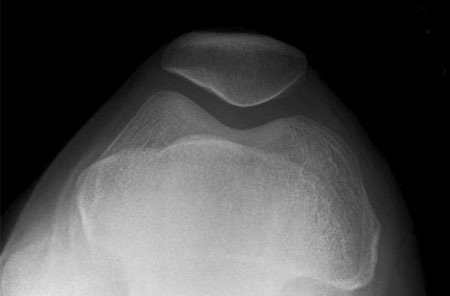

X-rays of the Knee:

These are done to diagnose problems in the bones and or joints

The common types of Knee X-rays a Knee Surgeon would require are

Knee (AP Weight-Bearing View)

Lateral Knee X-rays

Axial View